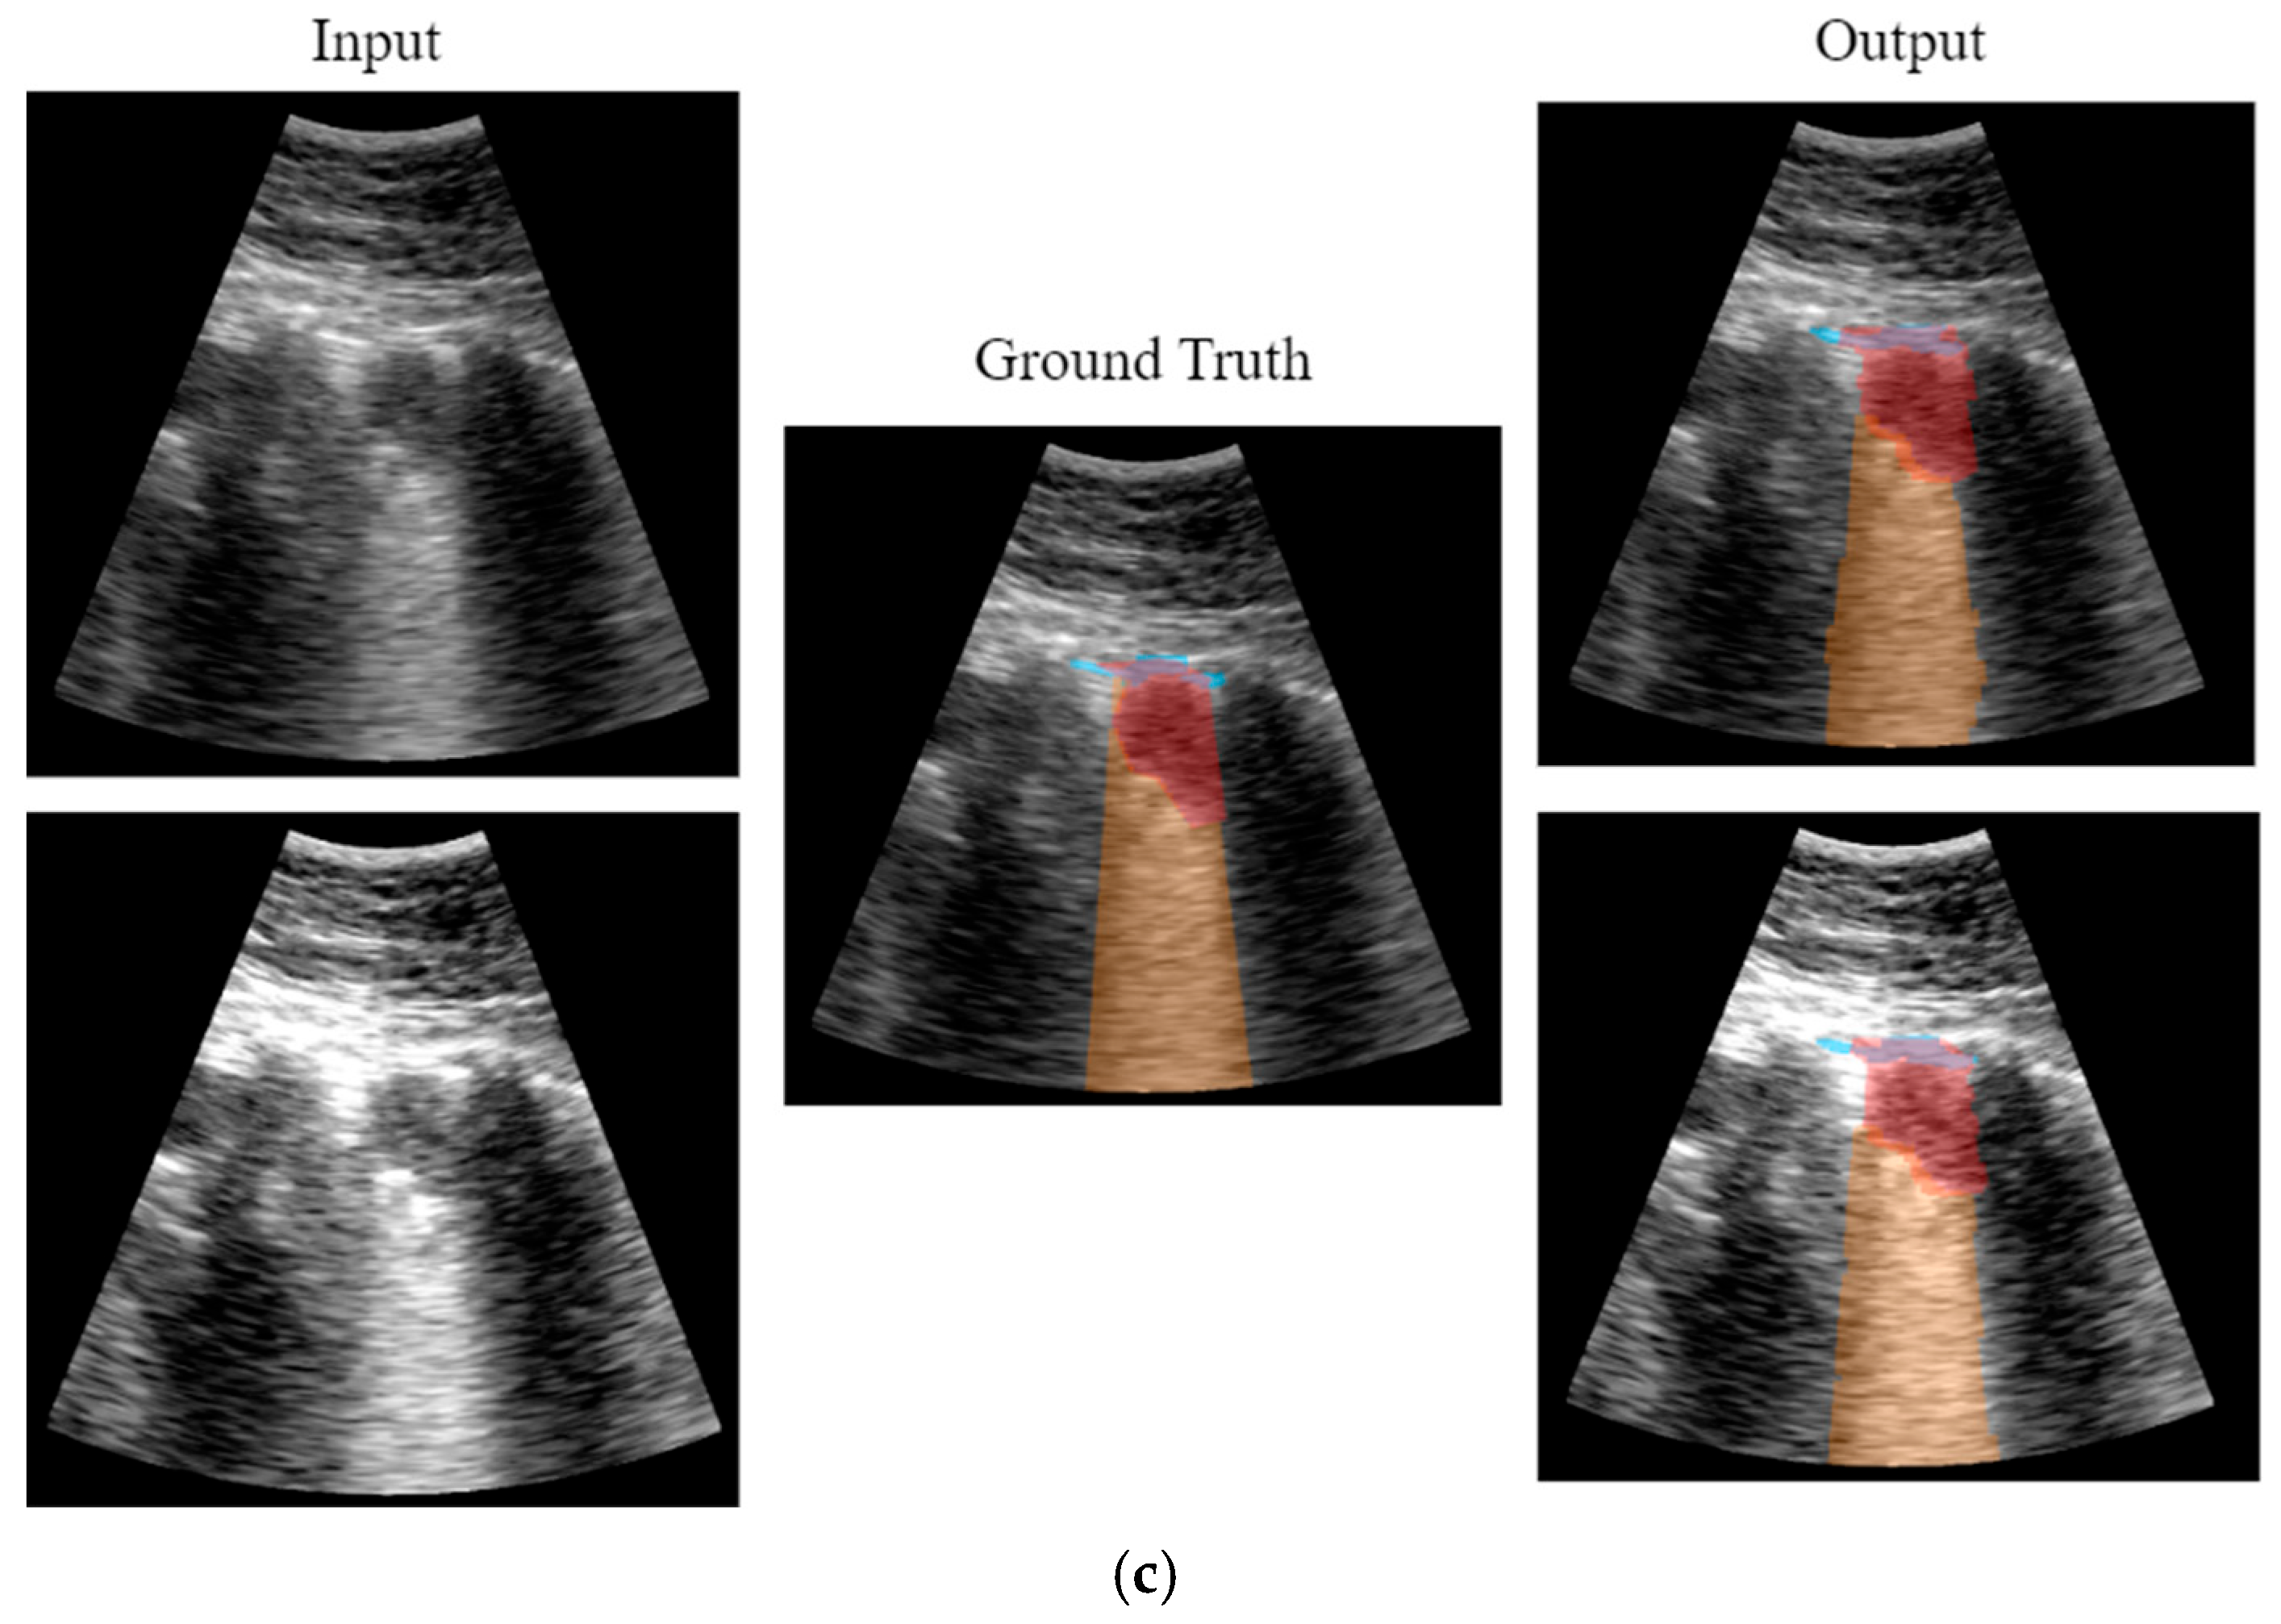

2.5.4. Visualization

3. Results

3.2. Real-Time Implementation Results